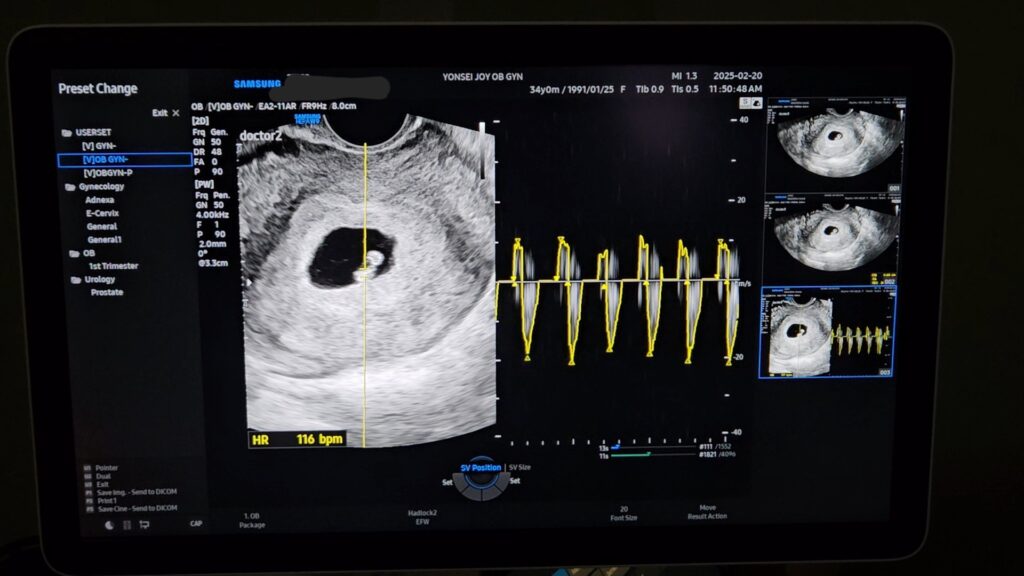

처음으로 심장소리를 들은 날.

초음파를 보니 고리 모양의 난황과 강낭콩 같은 작은 아기 형상이 있었고, 조그만 강낭콩 중간부에 초음파를 조준하니(?) 거기서 심장 소리가 나왔다.

심장소리를 들으니 눈물이 찔끔 났다.